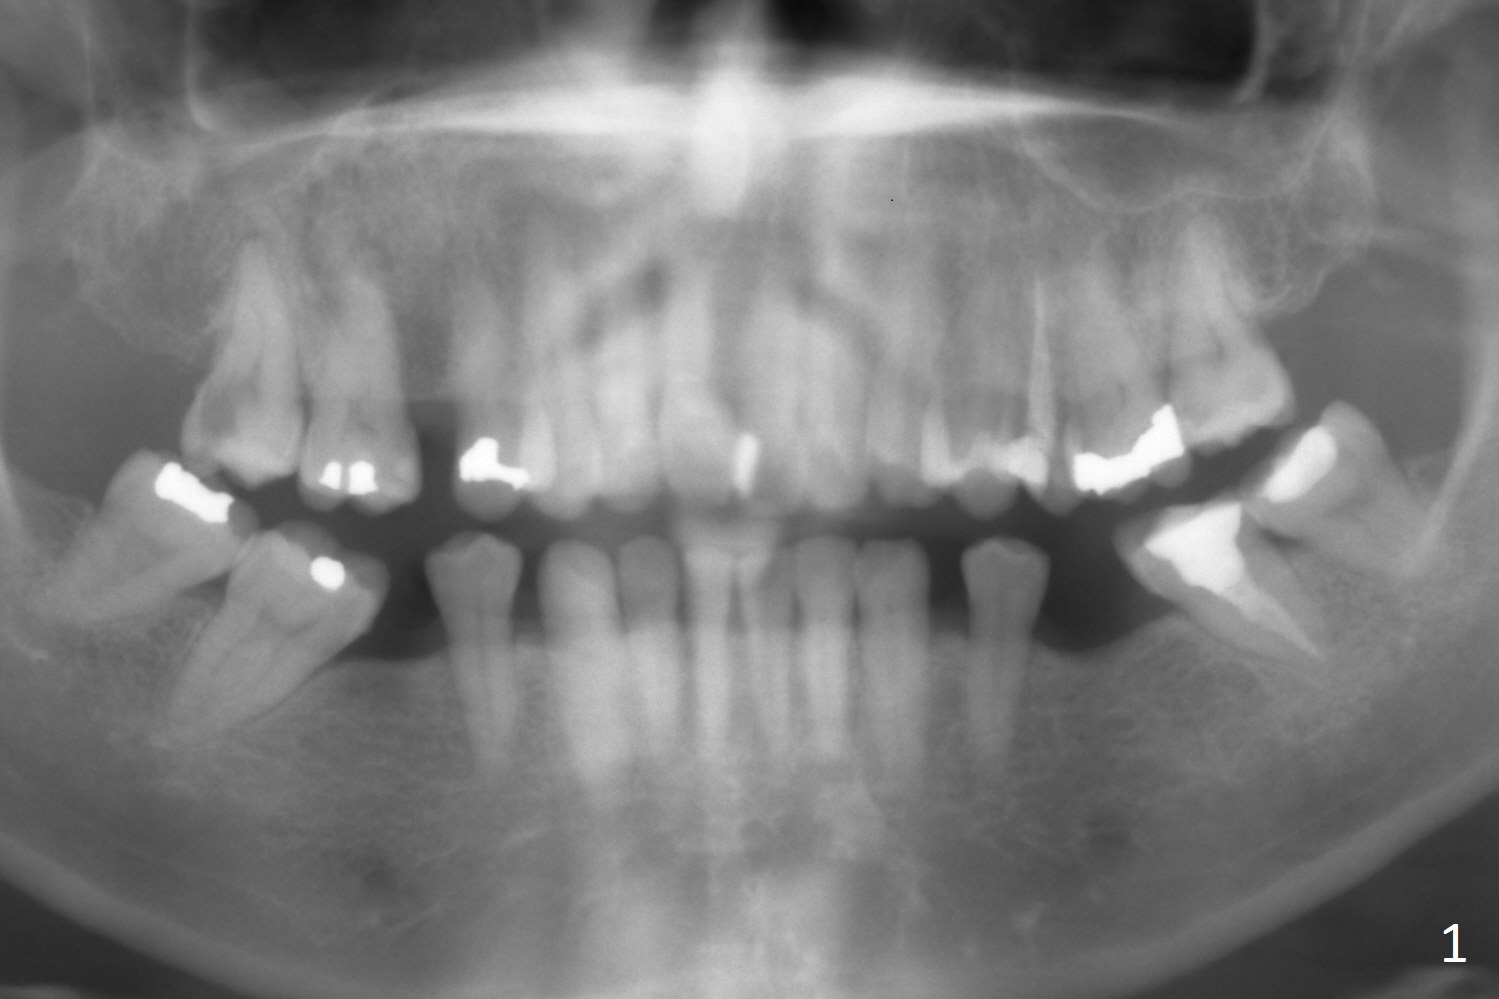

A 51-year-old woman requests extraction of the upper right 2nd molar (Fig.1) with caries and sensitivity (Fig.2 *). After discussion of treatment options including RCT, she chooses implant. The tooth has most likely fused roots and single socket. Try to use tap drills to form osteotomy palatal and deep.